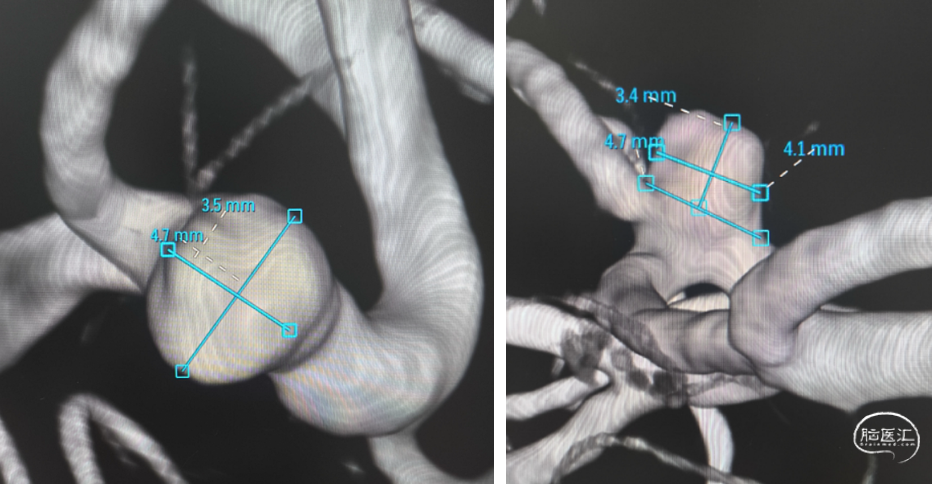

平均宽度(4.7+3.5)=4.1mm,最小深度3.4mm,选择SL6x2

右侧:平均宽度(5.5+3.9)=4.7mm,最小深度2.8mm,选择SL5x2

平均宽度(4.5+3.8)=4.2mm,最小深度7.5mm,选择SL5x3

3D测量动脉瘤:宽5.8mm,深5.1mm,SL6x3